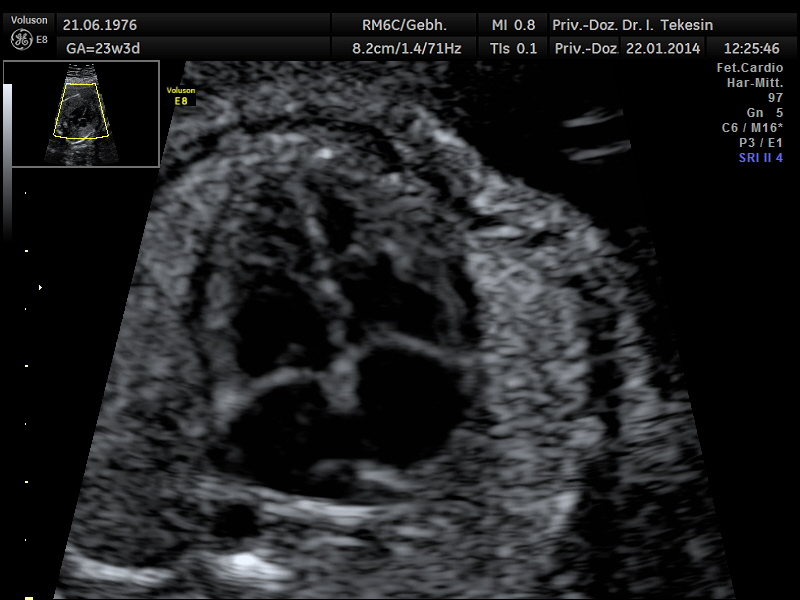

Fetale Echokardiographie

Ein weiterer Bestandteil der weiterführenden Ultraschall-Diagnostik ist die Beurteilung des kindlichen Herzens und der großen Blutgefäße, die fetale Echokardiographie. Dabei untersuchen wir die Lage, Größe und Symmetrie des Herzens, Anatomie der Herzstrukturen, Funktion der Herzklappen, Herzfrequenz und die Lage der großen Gefäße. Mit Hilfe der farbkodierten Doppler-Sonographie des Herzens werden weitere Details untersucht: die Funktion der Herzkammern, Herzscheidewände, Blutflüsse im Herzen und Blutflüsse in den großen Gefäßen.

Das Ziel dieser Ultraschalluntersuchung des fetalen Herzens ist der weitest mögliche Ausschluss von angeborenen Herzfehlern. Die Voraussetzung hierfür sind eine spezielle Ausbildung und Erfahrung des Arztes in Verbindung mit der hohen Qualität des Ultraschallgerätes.

Normaler Vierkammer-Blick

Normaler Vierkammer-Blick mit Farbe

Normales Herz in der 24. Woche

Normales Herz in der 22. Woche